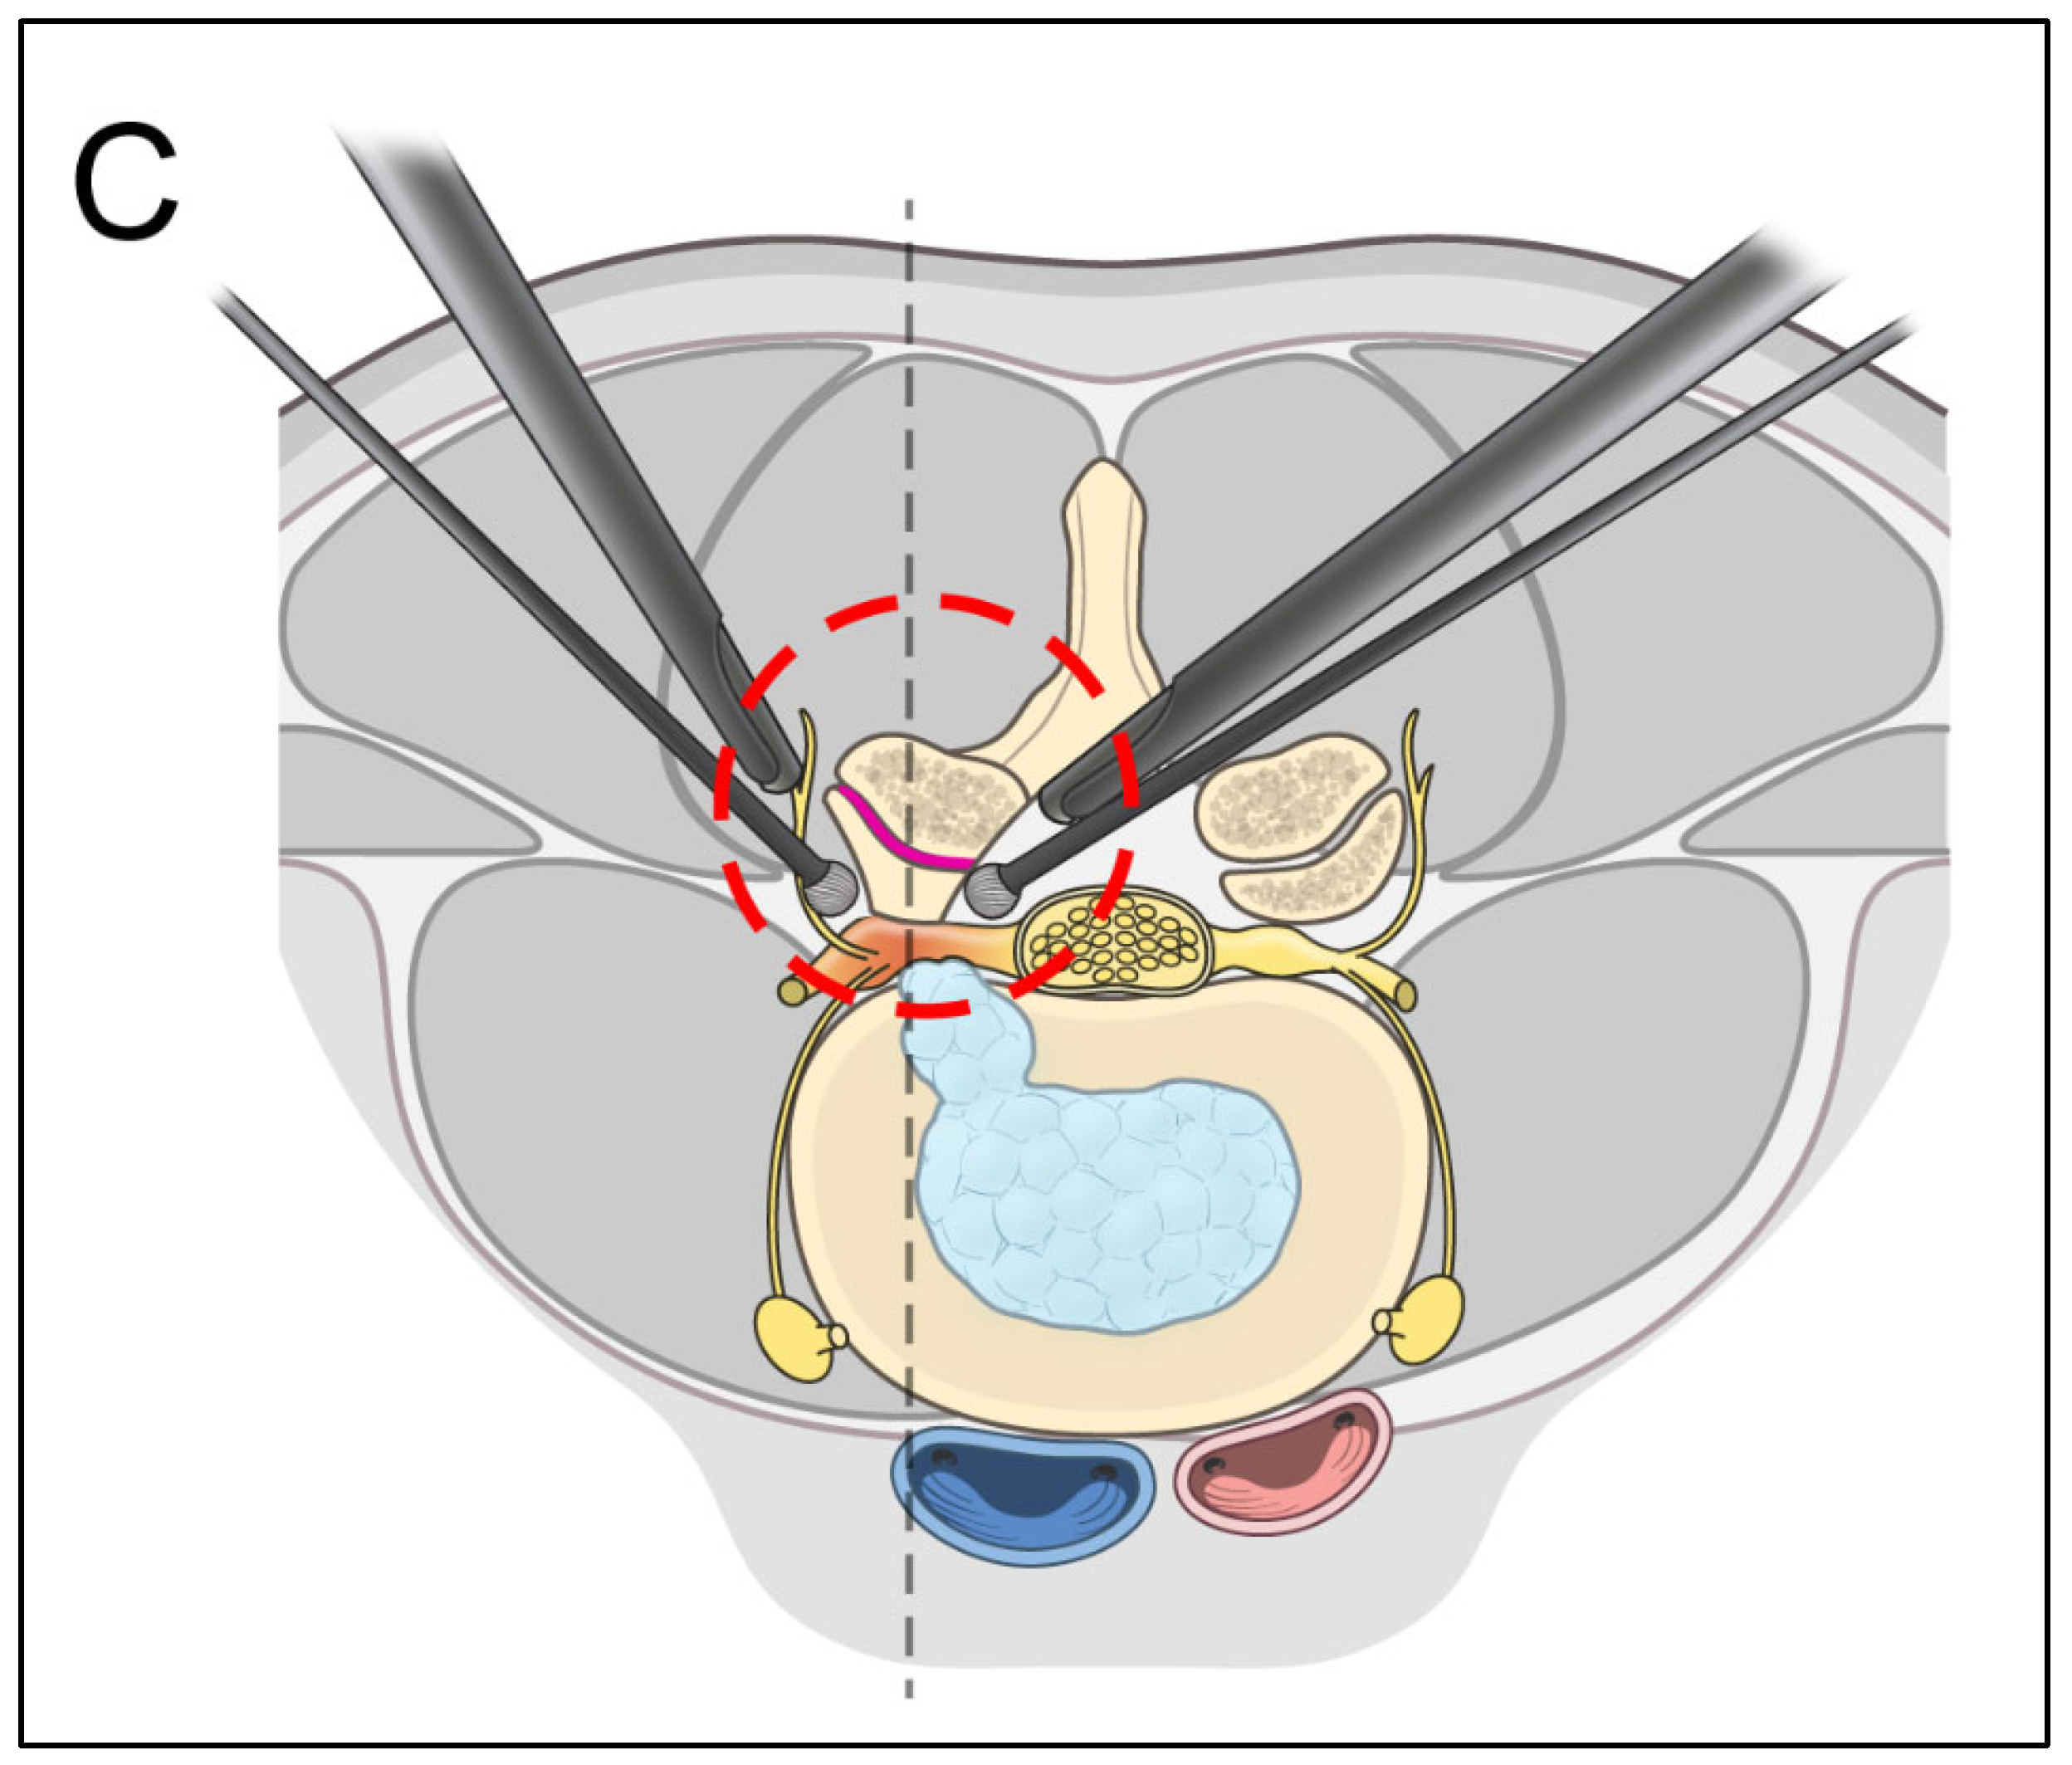

2.2. Surgical Procedure

2.2.2. Extraforaminal Approach